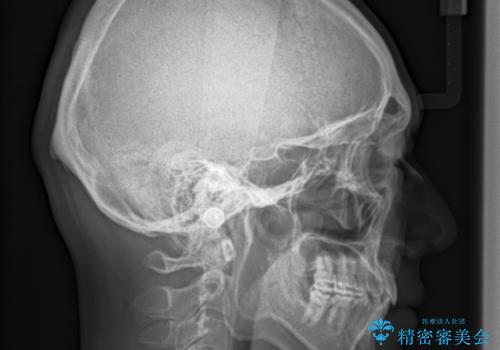

- 30代男性

- 以前、上下左右4本抜いてワイヤー矯正をしていた方で、後戻りで下の前歯のガタガタを気にして来院されました。

マウスピース矯正にて、下の歯はIPR(歯と歯の間を削る)を入れることでガタガタの改善、咬み合わせの深さも改善をはかる治療計画をたてました。